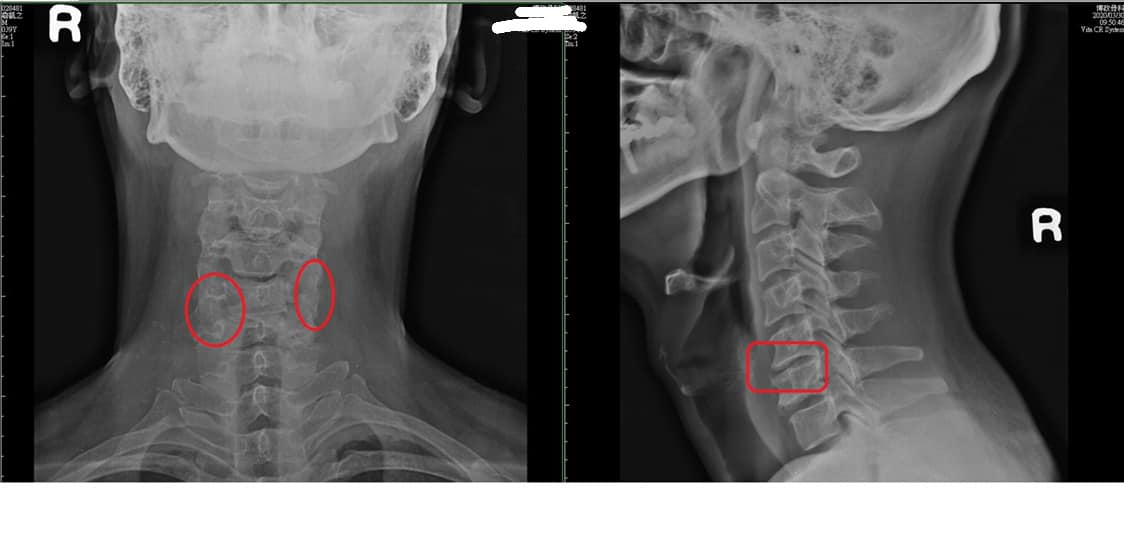

台北士林區詹先生抱怨1年前車禍受傷,先在中醫診所針灸三個月,又在新光醫院做整整1年的電療跟熱療,剛事故痛到手麻又沒力,才又去拍攝核磁共振,神外醫師看完片子建議開刀,由於患者畏懼開刀,就展開長達一年的中西醫復健,大約改善七成,但是每次平躺縮下巴頭旋轉就會強烈誘發左邊上臂痛,甚至手麻,就只剩這點一直沒改善⋯⋯⋯⋯⋯⋯

🆘診斷:神經根型頸椎病C5~C6

⭕️評估:患者手臂跟肩膀沒萎縮,肌力目前都正常,握力也沒問題,腳走路還沒問題,也沒有步態不穩的情況,也沒有肌反射增加,下肢肌肉張力正常,膝反射及足根反射正常,Babinski reflex正常,判斷中等程度神經根壓迫,還沒到嚴重脊髓病變,不過為了安心起見,先安排兩週治療,如果都沒有任何進步可以考慮新光醫院進行神外手術,或者疼痛科神經阻斷術